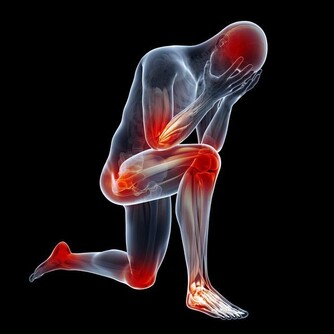

成為炎性反應- 表現是局部的紅、腫、熱、痛現象。

由於多了血液,膠原及組織液於傷口附近進行上面的過程, 壓力會刺激附近的神經線,

造成紅腫,麻痺和癢甚至脹痛!